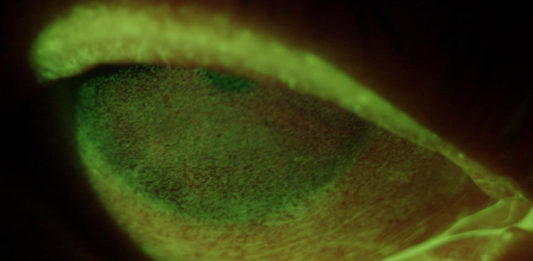

Giunge alla nostra osservazione al CIOS, Centro Italiano Occhio Secco presso CAMO, una paziente di 56 anni...

La dry eye disease (DED) è una condizione multifattoriale complessa, spesso difficile da diagnosticare per la scarsa...